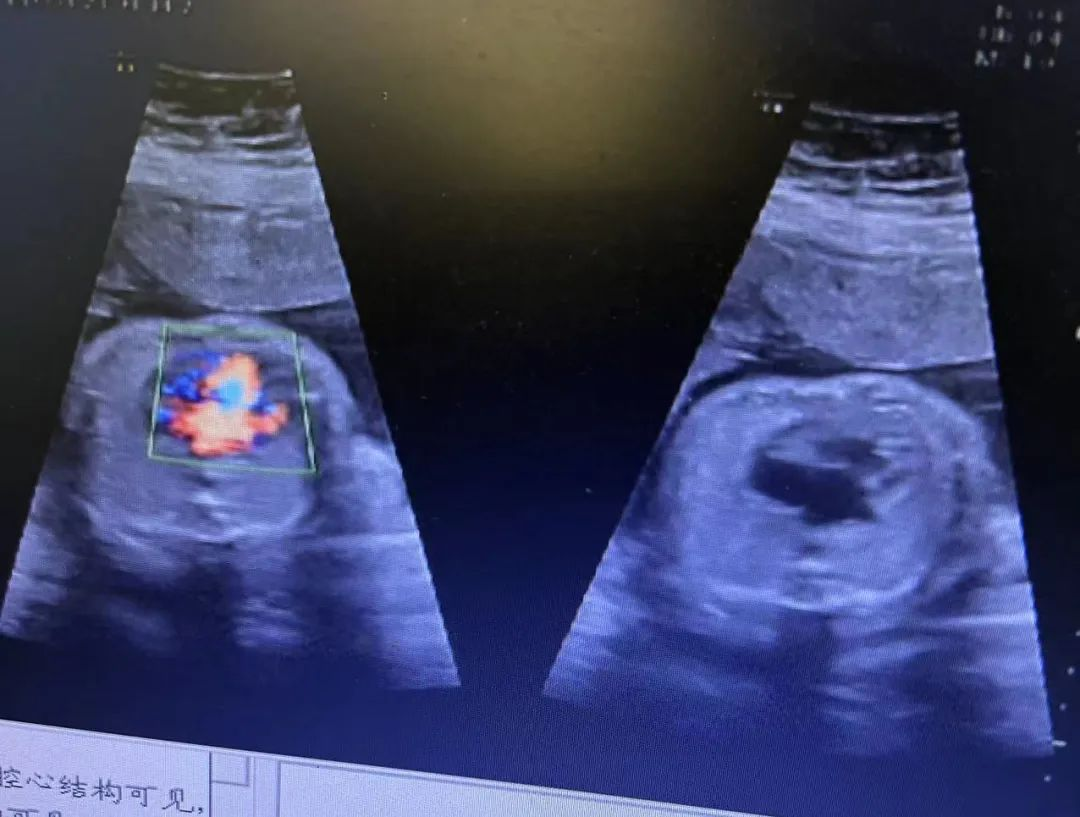

近日,我院超聲科醫(yī)生在給孕中期孕媽做四維彩超檢查時(shí),發(fā)現(xiàn)胎兒查出異常,孕媽想留下這個(gè)寶寶,陷入了兩難。

武漢的劉女士(化名),前幾個(gè)月剛懷上寶寶,全家都特別高興。懷孕23周+時(shí),劉女士在家人的陪伴下來(lái)到武漢仁愛(ài)醫(yī)院超聲科做了四維彩超檢查,當(dāng)醫(yī)生拿出檢查報(bào)告的時(shí)候,劉女士卻當(dāng)場(chǎng)傻眼了,原來(lái),在四維彩超的報(bào)告里,診斷出了胎兒右肺囊性腺瘤樣病變,她的心頓時(shí)揪了起來(lái)!

劉女士看到檢查結(jié)果后,擔(dān)心該病變會(huì)影響腹中寶寶的健康,考慮是否應(yīng)該終止妊娠。隨即,武漢仁愛(ài)醫(yī)院超聲科王娟主任為劉女士耐心地解釋?zhuān)?/span>“先天性肺囊腺瘤是一種肺組織錯(cuò)構(gòu)畸形,先天性肺囊腺瘤畸形病例約70%的腫塊大小較穩(wěn)定;約20%腫塊產(chǎn)前明顯縮小或消失;僅10%腫塊是進(jìn)行性增大。單純的先天性肺囊腺瘤(CCAM)無(wú)水腫的胎兒可以密切隨訪,在28周前接受連續(xù)超聲復(fù)查,CVR<1.6,一般超聲動(dòng)態(tài)監(jiān)測(cè)2~4周監(jiān)測(cè)一次,而對(duì)于CVR≥1.6的需要在28周前每周1-2次的超聲監(jiān)測(cè),防止出現(xiàn)胎兒水腫,直到分娩。”